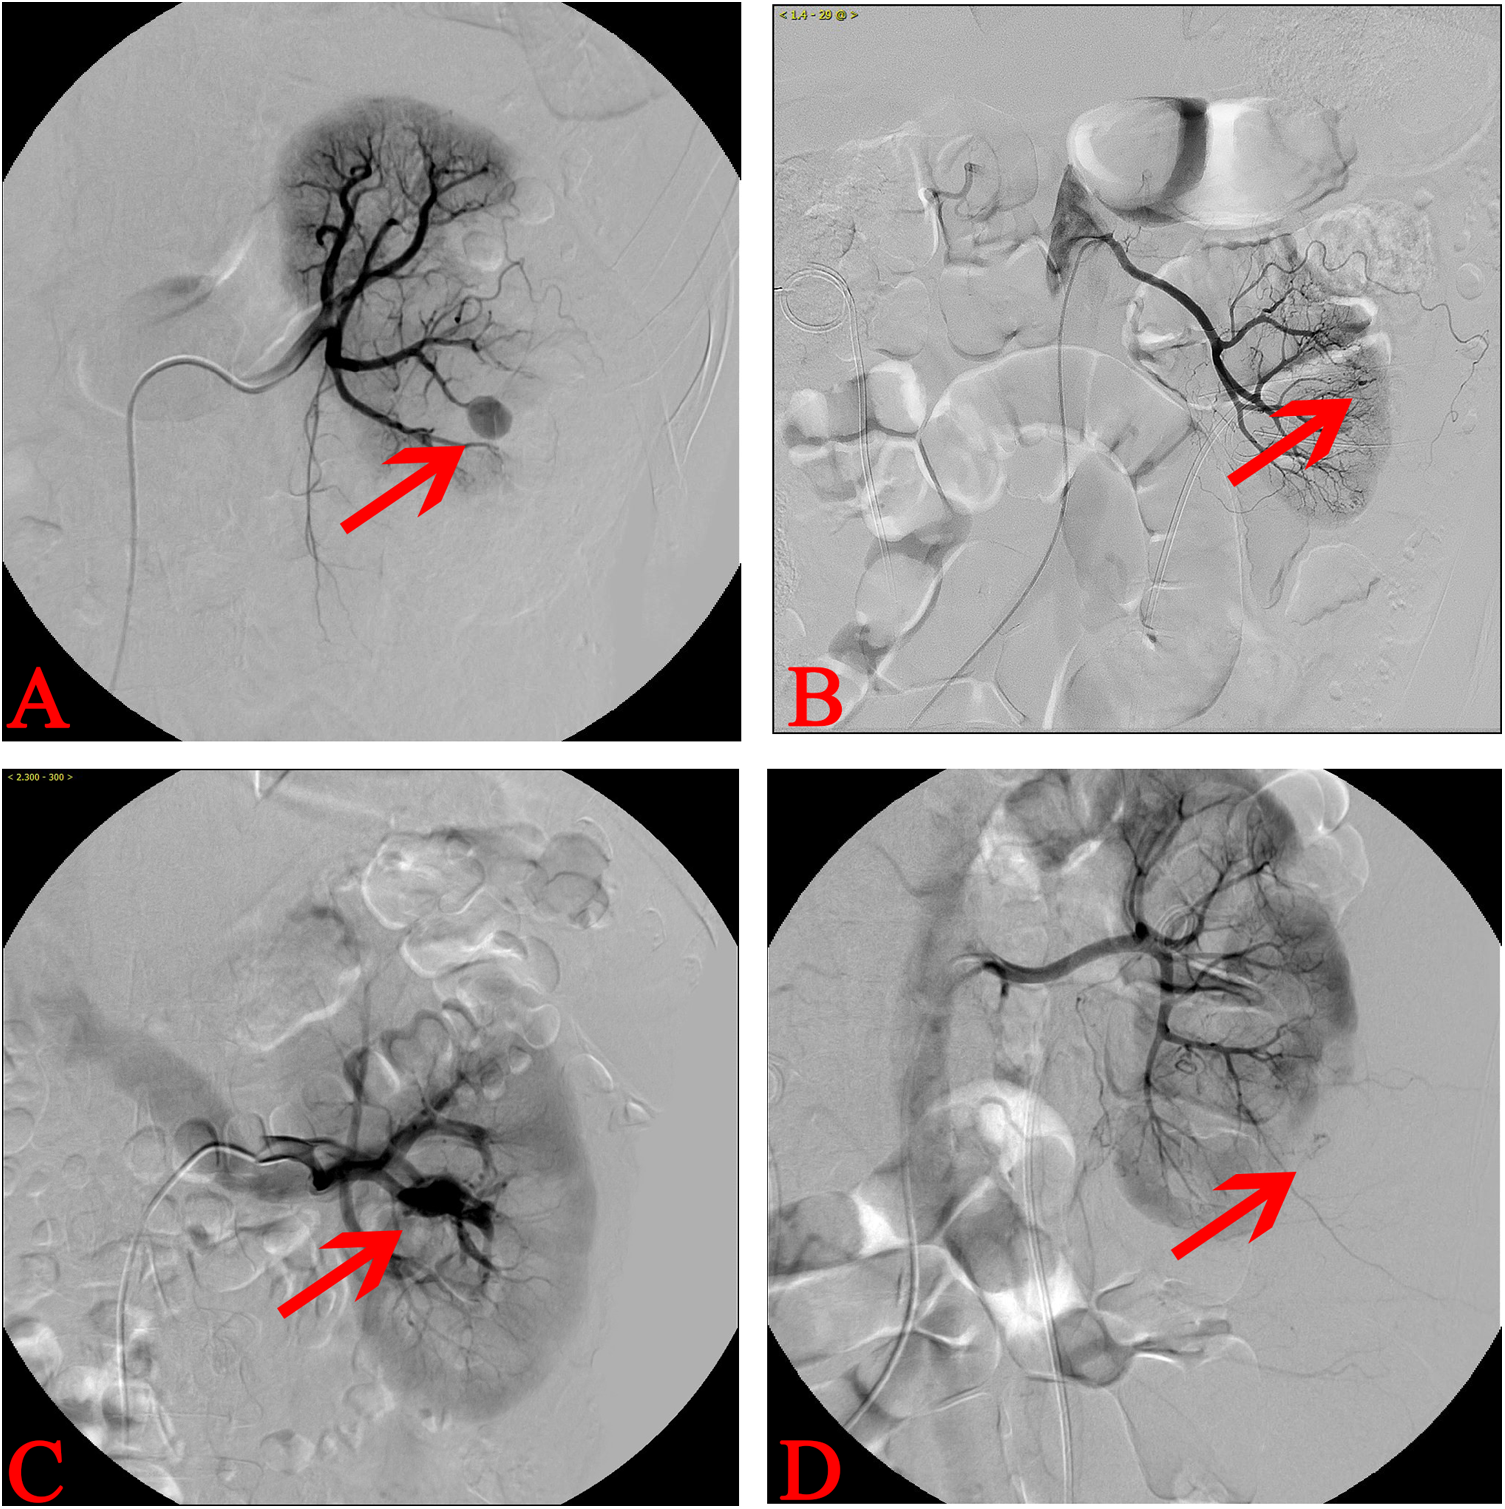

The types of vascular injuries among the 38 TAE patients were classified into four categories based on angiographic images and clinical bleeding characteristics: 18 cases of PA (Figure 2A), 12 cases of ACF (Figure 2B), 7 cases of AVF (Figure 2C), and 1 case of arterioperirenal fistula (APF) (Figure 2D). Given that only one patient with APF was included in the study, this patient was excluded from the statistical analysis. Only the clinical characteristics of patients with PA, ACF, and AVF were analyzed. Continuous data including age, BMI, urine leukocyte counts, stone size, Cr, TAE interval, Hb decrease, operation time, No. of tracts, and size of tract were analyzed via Kruskal–Wallis H(K) test. Categorical data including gender, urine culture, hydronephrosis, hypertension, diabetes, previous surgery, renal insufficiency, and bleeding type were analyzed using chi-square test. No statistically significant differences were observed among the three groups of patients in terms of gender, age, BMI, TAE interval, Hb decrease, operation time, stone size, preoperative urine routine white blood cell count, Cr level, and baseline disease status, such as hypertension, diabetes, history of previous surgeries, or renal insufficiency. The only parameter showing a statistically significant difference was the number of tracts (P = 0.032) (Table 2). And the post hoc test for pairwise comparisons of the number of tracts indicated the ACF group had more tracts than AVF group (Table 2).

Figure 2

www.frontiersin.org

Figure 2. Different types of artery injury after PCNL. (A) Left renal RA suggesting that PA is the most common type of vascular injury after PCNL. (B) Left RA showing the extravasation of contrast agent and indicating vascular injury. The patient had severe hematuria and was clinically classified as ACF. (C) RA revealing the contrast agents found in the renal veins early during angiography, which implies AVF. (D) Left kidney RA revealing the extravasation of contrast agent to the perirenal area with the inferior kidney compressed. The patients often showed decreased Hb with no evident gross hematuria, and imageological examinations usually suggest perirenal hematoma. This type of artery injury was APF.

In this study, we classified the types of vascular injuries into PA, ACF, AVF, and APF (Figure 2). PA is defined as a vascular injury where surrounding connective tissue forms an imaging characteristic similar to an aneurysm (6, 13, 14). AVF occurs when the artery and vein are involved in the injury, which leads to early arterial blood entering the vein (6, 13, 14). ACF refers to an arterial injury connected to the collecting system (10). APF includes an arterial injury connected to the renal capsule. This type of injury has not been previously reported but may be associated with compression of the renal capsule following bleeding. The patients typically present with a decrease in Hb level, accompanied with back pain and a relatively clear urine color. In addition, imaging examinations often reveal massive retroperitoneal hematoma.